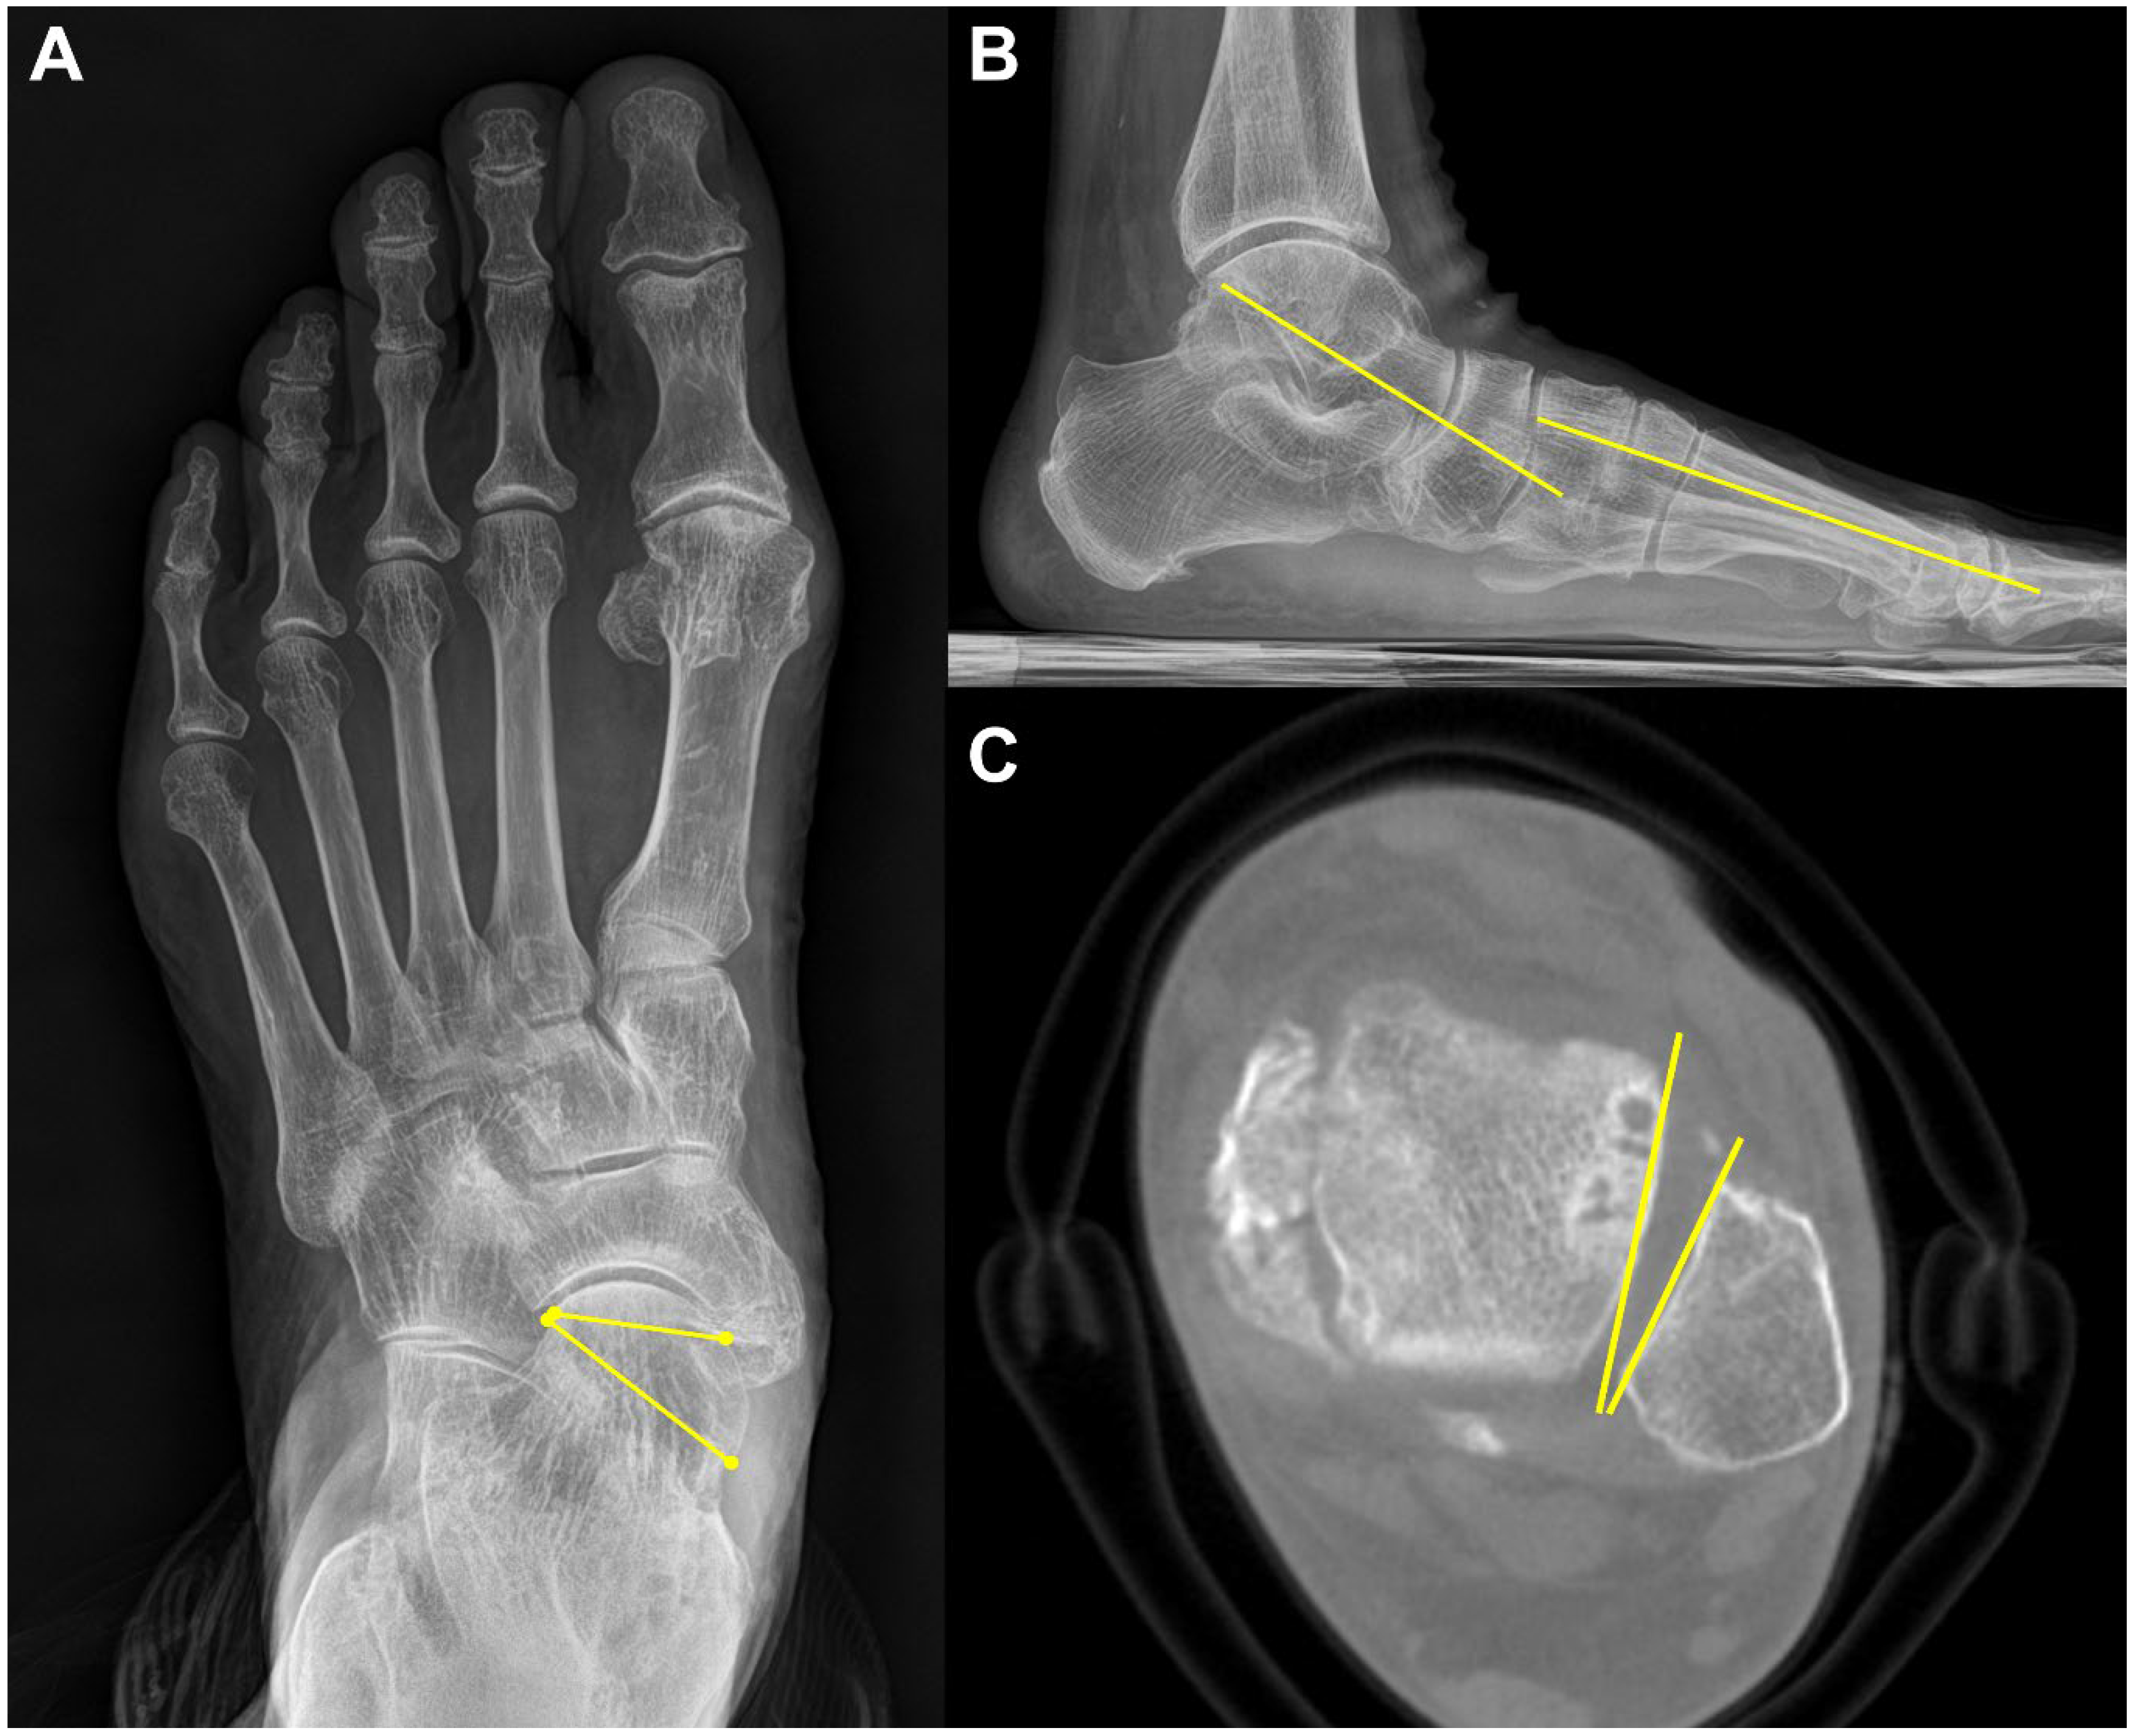

3.2. Midfoot Osteoarthritis

In the midfoot, precise identification of associated articulations and osseous borders in conventional weight-bearing radiographs may not be handy because they can be affected by overlapping adjacent bones when viewed two-dimensionally [31] (Figure 6). For this reason, WBCT is an alternative, as it enables clear joint space visualization and enhanced bony landmark identification under physiological weight-bearing conditions. Steadman et al. compared weight-bearing radiographs and WBCT with regard to diagnostic accuracy in midfoot osteoarthritis [32]. They found that weight-bearing radiography demonstrated 61.5 to 72.5% sensitivity and 87.9 to 96.1% specificity in identifying midfoot osteoarthritis. It also showed less accurate localization of degenerative changes and a greater tendency to underestimate disease severity compared to WBCT. These findings indicate that WBCT would be a better diagnostic option in midfoot osteoarthritis as it provides an earlier and more reliable diagnosis.

Figure 6.

In the plain radiograph, osteoarthritis of the third tarsometatarsal (TMT) joint is not clearly visible (A, See box area); however, weight-bearing computed tomography (WBCT) reveals distinctive joint space narrowing and sclerotic changes (B,C; See arrow).